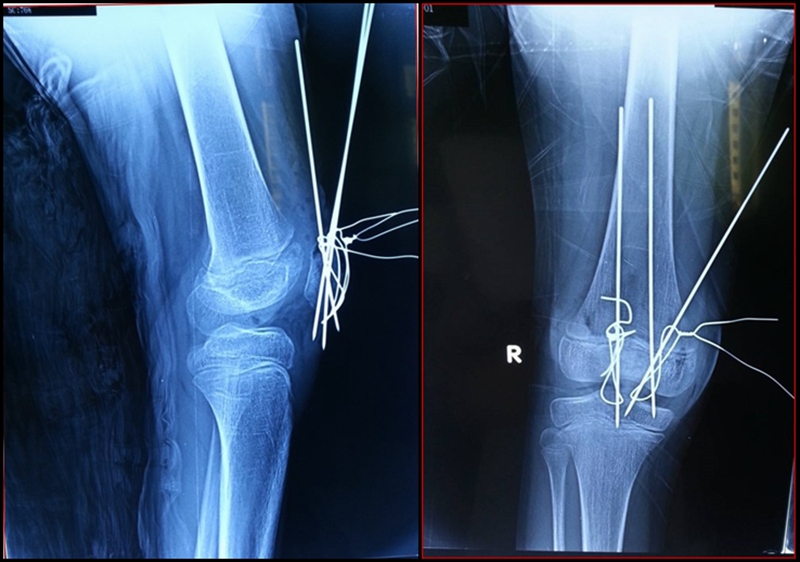

图1 受伤当时X线片

图2 受伤3周X线片